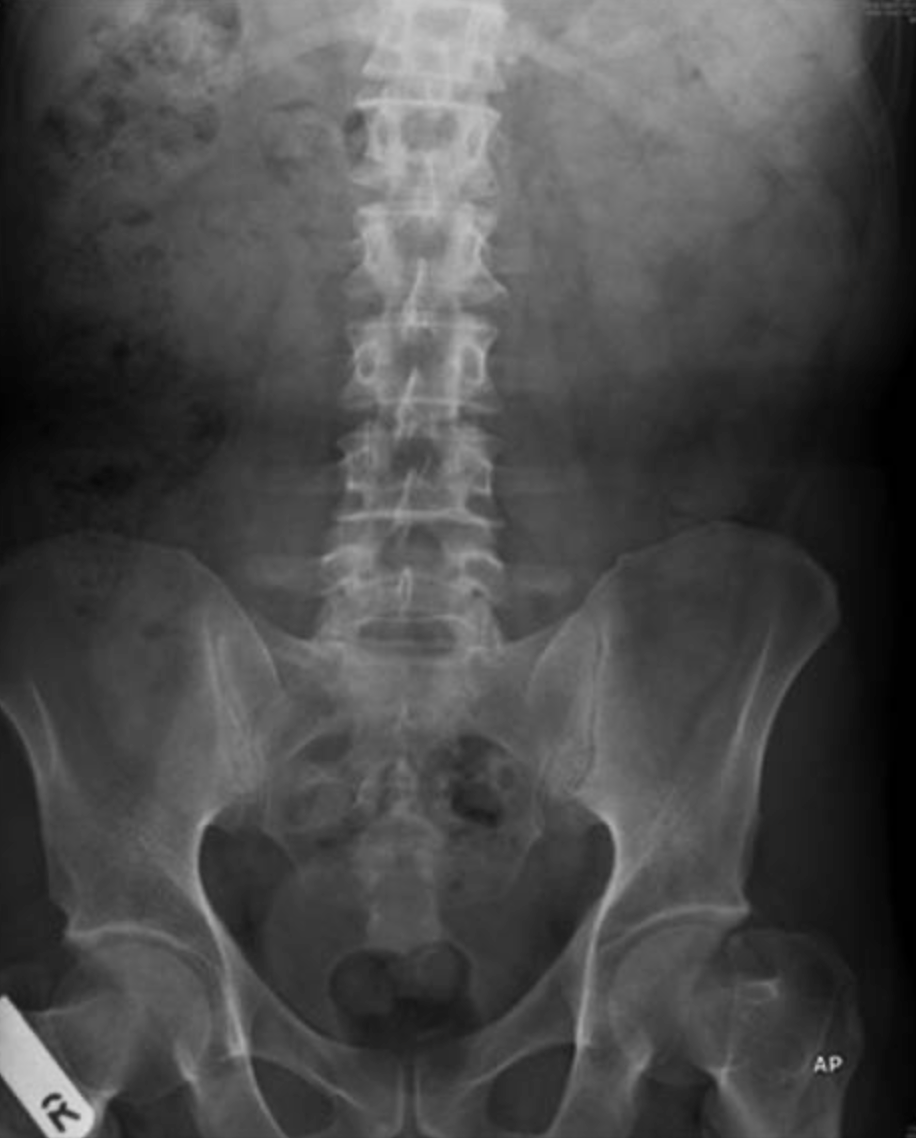

腹部X光片未见异常。

腹部CT显示肝脏IV段有一处边缘强化的不规则低密度灶,大小约5.6×7.5×7.7 cm,与肝脓肿相符。同时,在IV B段肝脏下缘可见一条高密度线状异物,贯穿肝组织,长度约2.5 cm。胆囊形态无异常。胰腺、脾脏、肾上腺和双肾均正常。影像学提示:这是由于肝内异物引起的脓肿。